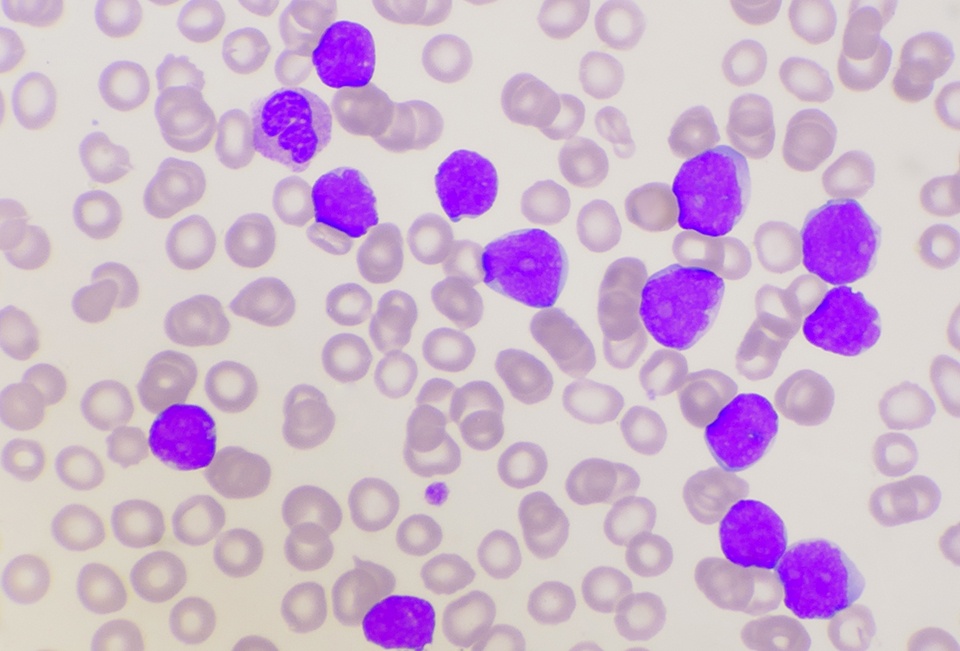

A study found key tumor heterogeneities, including Ki-67 indices, might contribute to disease progression in GEP-NETs.Patrick DalyGEP-NETs | March 19, 2025

Lu-177-dotatate in PRRT appeared to treat GEP-NETs, though prior internal radiation may impede responses or worsen survival.Patrick DalyColorectal Cancer | March 19, 2025